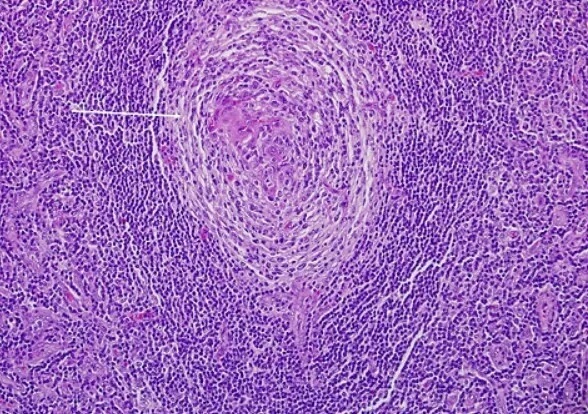

Castleman hastalığının teşhisi, fizik muayene, kan testleri, görüntüleme teknikleri (örneğin, BT taraması veya MRI) ve lenf bezinin biyopsisi ile yapılır. Biyopsi, lenf bezinin bir örneğinin mikroskop altında incelenmesini içerir ve hastalığın türünü ve şiddetini belirlemede hayati önem taşır. Tedavi, hastalığın türüne, şiddetine ve hastanın genel sağlık durumuna bağlı olarak değişir. UCD genellikle cerrahi olarak tedavi edilirken, MCD için daha kapsamlı bir yaklaşım gerekebilir.